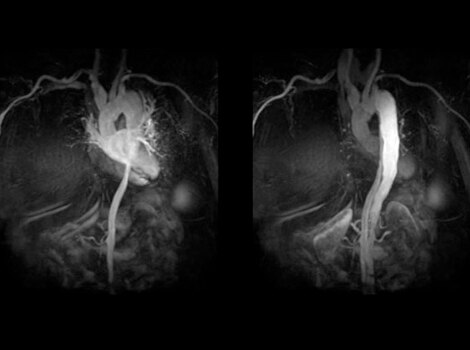

Cardiac MR

CINE IR optimal TI value for MDE in a rapid, single breath-hold.

Revolution CT & CardioGraphe4

Achieve one-beat, whole heart acquisition for imaging or comprehensive cardiac assessment with or without beta blockers at any heart rate.5

If considering catheter ablation as a treatment option, pre-procedure planning can involve use of MR or CT imaging to identify anatomical targets for the procedure and understand the extent of AF. These images can help guide decisions on necessity of left atrial appendage closure in certain populations.3